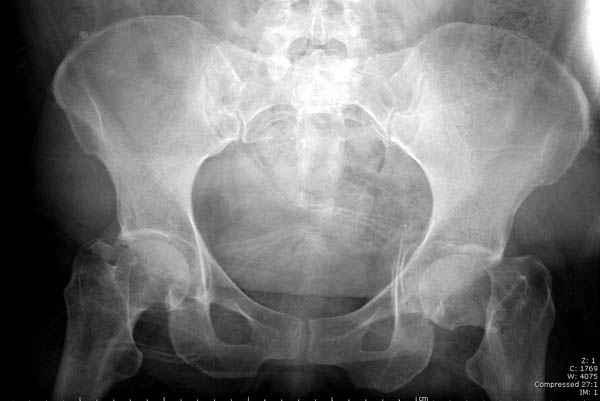

Уважаемые коллеги! С прошедшеми Вас праздниками. Теперь ближе к трудовым будням. Поступила 16 летняя девушка неделю назад. Механизм травмы падение с 5 этажа. Краткий диагноз:закрытый перелом левой ключицы, левого плеча, закрытый вертикально и ротационно нестабильный перелом костей таза:закрытый перелом левой подвздошной кости, переломы лонной кости справа, перелом обоих колонн вертлужной впадины слева;субкапитальный перелом шейки левой бедренной кости со смещением. По тактике лечения таза возникли следующие вопросы: 1. С чего начать - фиксации переломов вертлужной впадины или устранения деформаций таза? 2. Надо ли фиксировать шейку или фиксировать бедро в аппарате вместе с тазом, а после сращения таза планировать ТЭП ТБС? Если имеются еще какие подводные камни, будем рады выслушать.Спасибо.

На снимке ацетабулума редко встречающийся очень низкий перелом, наверное, трудно было репозицию через один доступ? Перелом как бы замкнулся в квадрилатеральной поврехности.